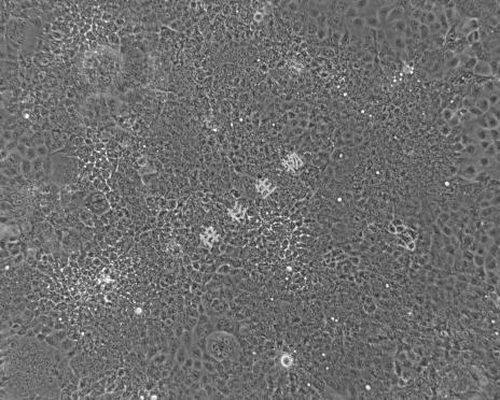

细胞形态: | 上皮细胞样 |

生长特性: | 贴壁生长 |

图片展示